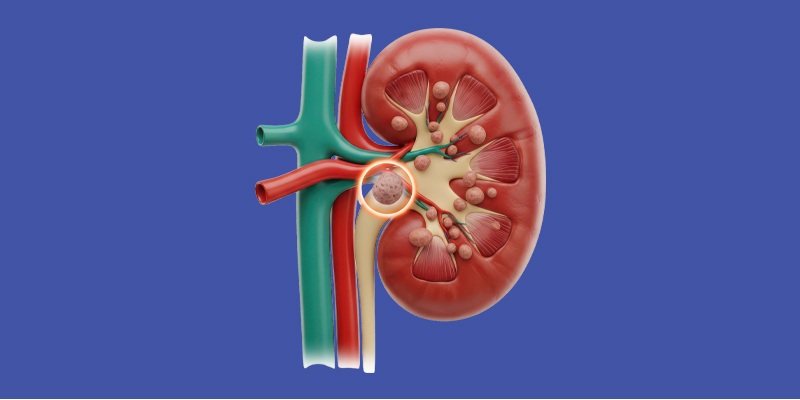

Kidney Stone Disease